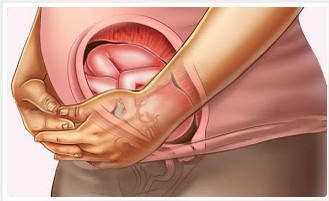

Seus ossos, cartilagens e músculos começam a ficar cada dia mais firmes e fortes2. Os pequenos chutes e cotoveladas já são intensamente sentidos pela mamãe. Daqui a pouco essa sensação poderá ser compartilhada com o papai, que ao colocar a mão sentirá os movimentos do seu herdeiro ou princesa.